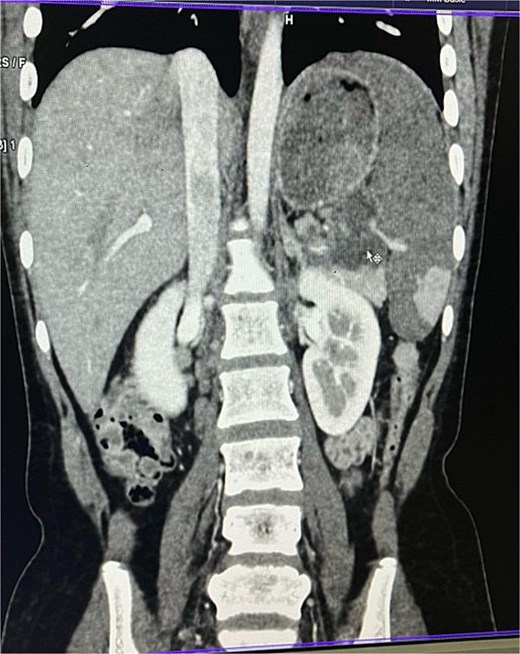

On imaging, ultrasonography showed a lobulated hypoechoic lesion in the region of the pancreatic tail and splenic hilum. This was very not conclusive, so a contrast-enhanced CT scan was planned, which revealed multiple necrotic, conglomerated lymph nodes (30 × 33 × 38 mm) near the splenic hilum and pancreatic tail, abutting the stomach and spleen, with maintained fat planes (Fig. 1). A splenic infarct involving a significant portion of the parenchyma was noted (Fig. 2), with multiple additional necrotic nodes along the retroperitoneum (paraaortic and iliac vessels) and mild pelvic free fluid. Then, CT-guided biopsy from the lymph nodal mass was planned, which showed moderately cellular smears showed caseous necrotic debris, lymphocytes, and clusters of epithelioid cells, suggestive of chronic necrotizing lesion consistent with TB.

Contrast enhanced computer tomography (CECT) abdomen showing necrotic lymph node mass near pancreatic tail and splenic hilum.